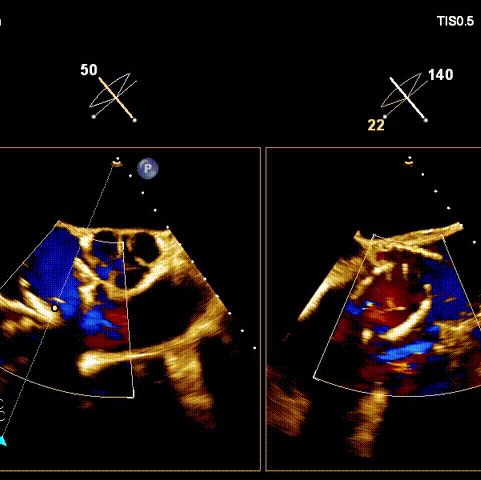

術前超聲

術后超聲

術前經過全面系統的評估后,考慮患者存在高齡、心功能減低、三尖瓣瓣環重度擴張(三尖瓣極重度反流)等高危因素,因此廈心結構心團隊聯合超聲心動、麻醉及護理團隊,制定了詳盡的圍術期治療方案及術中治療難點預案。術中,由王焱院長主刀,在蘇茂龍主任超聲心動團隊的輔助,上海市第一人民醫院陸方林主任的協助下,僅用時30分鐘,即順利完成了三尖瓣原位置換的手術。術中患者血流動力學穩定,術后即刻顯示LuX-Valve Plus瓣膜位置良好,固定穩定,瓣膜功能正常,無瓣周漏。

接受手術的為一名80歲男性,因“心悸2年,氣喘伴下肢水腫半年”入院。超聲心動提示“極重度三尖瓣反流,右房及右室明顯擴大,右心收縮功能輕度減低,左心收縮功能正常,肺動脈壓力正常”。患者同時合并有“持續性房顫”及“慢性心力衰竭”,病史持續2年,規律口服抗凝及強心、利尿治療治療效果不佳,癥狀持續。經廈心心臟團隊評估后,認為患者三尖瓣極重度反流并伴有心衰表現,長期內科藥物治療效果不佳,且患者高齡、外科手術風險高,因此決定采用微創經頸靜脈LuX-Valve Plus三尖瓣置換系統為患者治療。